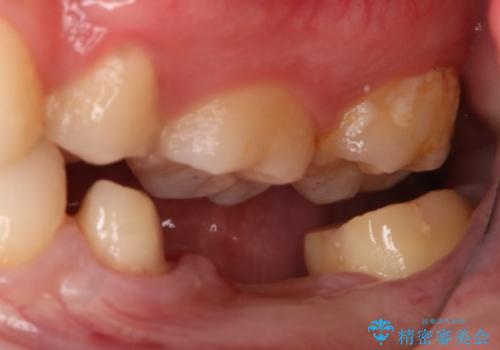

- 左下奥歯のブリッジのやり変え希望のため来院された患者様です。

支台歯部分はインレー形態でしたが強度や維持性を考慮しクラウン形態への変更を計画しました。

後ろの歯が前に倒れ込んでいましたが問題なく治療を終えることが出来ました。